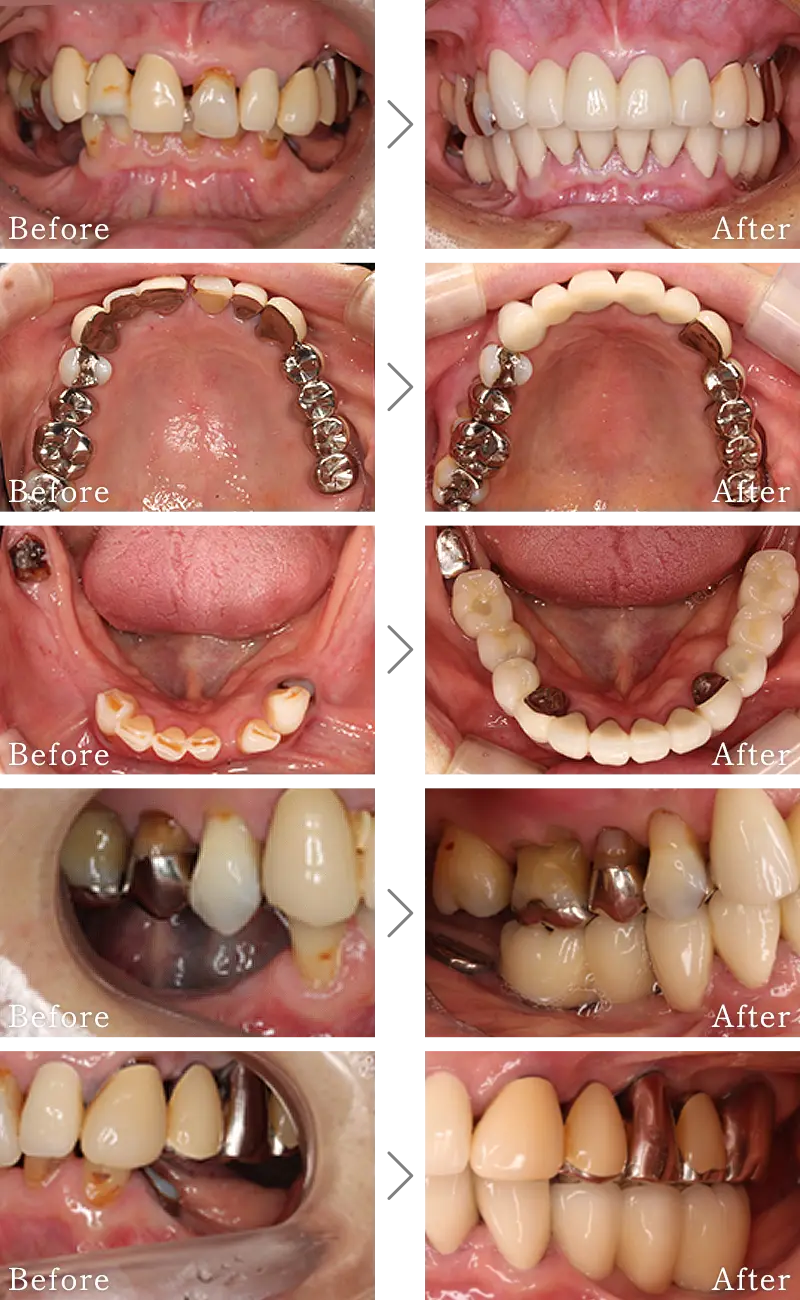

セラミック治療は、本物の歯のように白く自然な透明感のある「セラミック」という素材を用いて行う治療です。虫歯の治療で歯を削った後は、金属(いわゆる銀歯)で補う方法が一般的ですが、白い歯とかけ離れた見た目に不満を持たれる方を多いと思います。

セラミックは見た目の美しさはさることながら、硬さも天然の歯に近く、機能面でも申し分ありません。

銀歯やプラスチックの詰め物・被せ物は、長年使用すると徐々に変形し、虫歯再発の大きな原因となります。しかし、セラミックは物性が化学的に安定しているので変形することがなく、虫歯の再発リスクを大きく減らします。また、セラミック特有の滑らかな表面が汚れが付きにくくし、歯周病の誘発を抑える特長もあります。